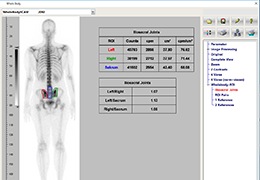

Performs 3D reconstruction and volume rendering.

Instant and interactive surface extraction and export to STL and PLY formats.

Side-by-side comparative assessment for pre- and post-operative scans.